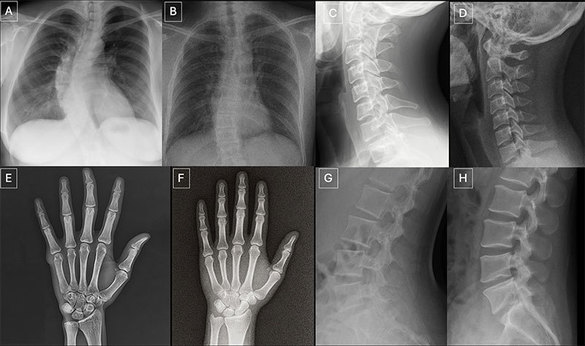

Radiografii reale şi radiografii generate de GPT-4o, pentru aceleaşi regiuni anatomice: (A) radiografie toracică postero-anterioară reală şi (B) generată de GPT-4o, (C) radiografie reală a coloanei cervicale în incidenţă laterală şi (D) generată de GPT-4o, (E) radiografie reală a mâinii în incidenţă postero-anterioară şi (F) generată de GPT-4o, precum şi (G) radiografie reală a coloanei lombare în incidenţă laterală şi (H) generată de GPT-4o. Perechile arată că GPT-4o poate produce imagini radiologice plauzibile pentru diferite regiuni anatomice. Credit: RSNA, 24 martie, 2025